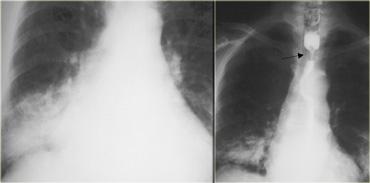

Hình bên trái là bệnh nhân không có triệu chứng với u cơ trơn thực quản.

Trên phim ngực thẳng, quan sát thấy một đám mờ bất thường phía sau tim (mũi tên).

Hình chụp thực quản cản quang barium cho thấy một khối có múi (mũi tên) không gây tắc nghẽn mặc dù kích thước lớn.

Trên phim X-quang, khối u (mũi tên) lồi vào ngách azygô-thực quản.

Trên hình chụp thực quản cản quang, bờ dưới của tổn thương trong thành này tạo thành góc gần vuông (mũi tên) với thành thực quản.

Một khối thực quản có vôi hóa hầu như luôn luôn là u cơ trơn.

Hình bên trái là bệnh nhân có tổn thương thực quản vôi hóa (mũi tên) lồi vào ngách azygô-thực quản trên phim X-quang.

Tổn thương (mũi tên) trên CT và phim X-quang bệnh phẩm phẫu thuật cho thấy hình ảnh vôi hóa.